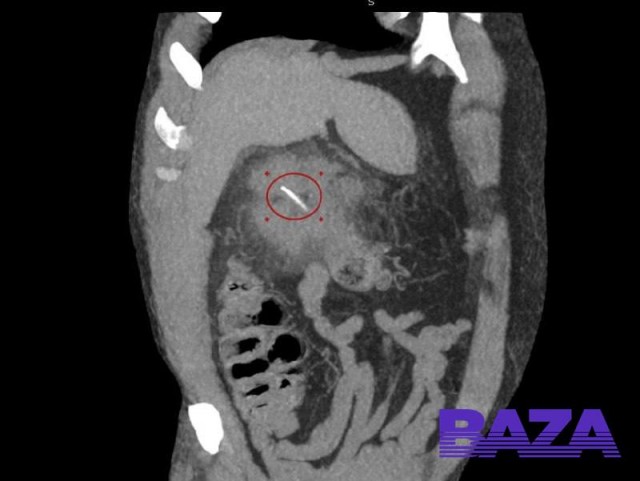

Он случайно проглотил кость, и она проткнула ему кишечник.

Около месяца назад 64-летний мужчина удачно сходил порыбачить и поужинал свежайшей рыбой. Несколько недель всё было нормально, но затем у рыбака начало покалывать в подреберье. Сначала мужчина терпел, а когда боль стала невыносимой, пошёл в больницу.

Врачи просветили пациента и нашли причину боли — ею оказалась рыбная кость. Она проткнула кишечник и подошла близко к печени. Медики Луховицкой больницы вскрыли абсцесс под спинальной анестезией и удалили кость. Рыбак уже идёт на поправку. Кажется, первое время после операции он будет выбирать только филе.

Рыбак из Подмосковья едва не погиб, поужинав жареной рыбой